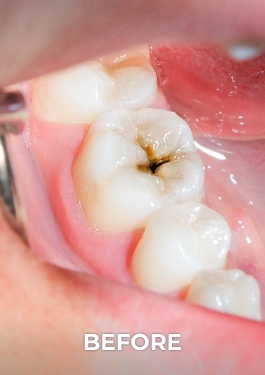

Root Canal Before and After in Mexico

Want to regain confidence in your smile? Our root canal gallery shows you real results: root canal pictures before and after that tell stories of transformation. Leave the pain and worry behind, and welcome a radiant, healthy smile. With our team of endodontic experts, each case is approached with care and precision, guaranteeing results that will take your breath away.